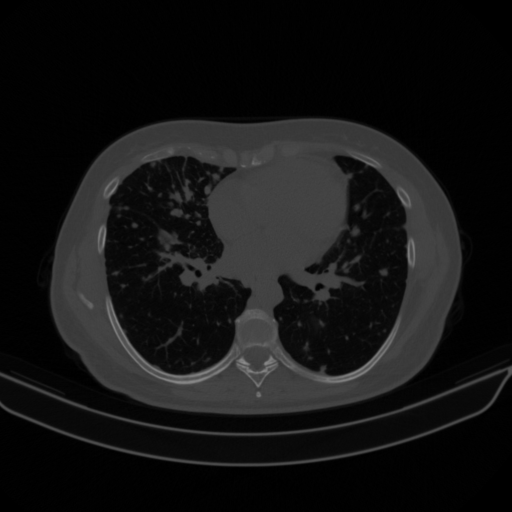

Original VENOUS CT scan

Full window (WL 1023.5, WW 4095 β†’ Low βˆ’1024, High +3071)

Lung window (WL -600, WW 1500 β†’ Low βˆ’1350, High +150)

Mediastinum window (WL 40, WW 400 β†’ Low βˆ’160, High +240)